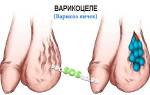

При варикозном расширении вен нижних конечностей крайне важно не упустить патологические изменения в области живота и паха, так как их наличие свидетельствует о нарушении кровообращения в подвздошной и нижней полой венах.

Такое состояние при длительном застое увеличивает риск развития варикоцеле. Расширение вен в яичках может проявляться болевыми ощущениями, асимметрией мошонки и увеличением вен семенного канатика. Повышенная температура в яичках со временем может привести к бесплодию.